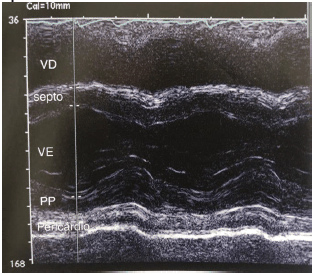

O traçado de modo M abaixo nos mostra um pericárdio espessado que se move com o epicárdio durante o ciclo cardíaco.

Na diferenciação entre uma pericardite constritiva e uma miocardiopatia restritiva, analise as afirmativas abaixo.